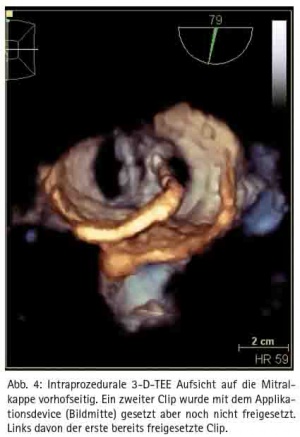

Im Rahmen des Mitra-Clip™-Verfahrens wird ein spezielles Kathetersystem über eine Leistenvene eingebracht und nach transseptaler Punktion kann der Mitra-Clip entsprechend in der maximalen Insuffizienz unter simultaner transösophagealer 3D-EchoKontrolle platziert werden (Abb. 4). Der Eingriff wird in Vollnarkose durchgeführt. Eine Sternotomie oder der Einsatz einer Herz-Lungen-Maschine ist nicht erforderlich. Sollte es dennoch einmal zu einer Notfallsituation kommen, ist ein sofortiges herzchirurgisches Eingreifen jederzeit möglich.